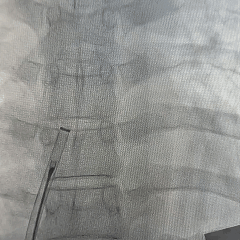

左盘展开

DSA下左盘展开

左盘面贴靠房间隔

右盘展开

固定钢缆,后撤鞘管展开右盘

DSA下牵拉试验

验证封堵器稳定夹持于缺损处

成型锁定

前顶钢缆和鞘管,牵拉成型线锁定封堵器

DSA下逆时针旋转解脱钢缆,释放封堵器